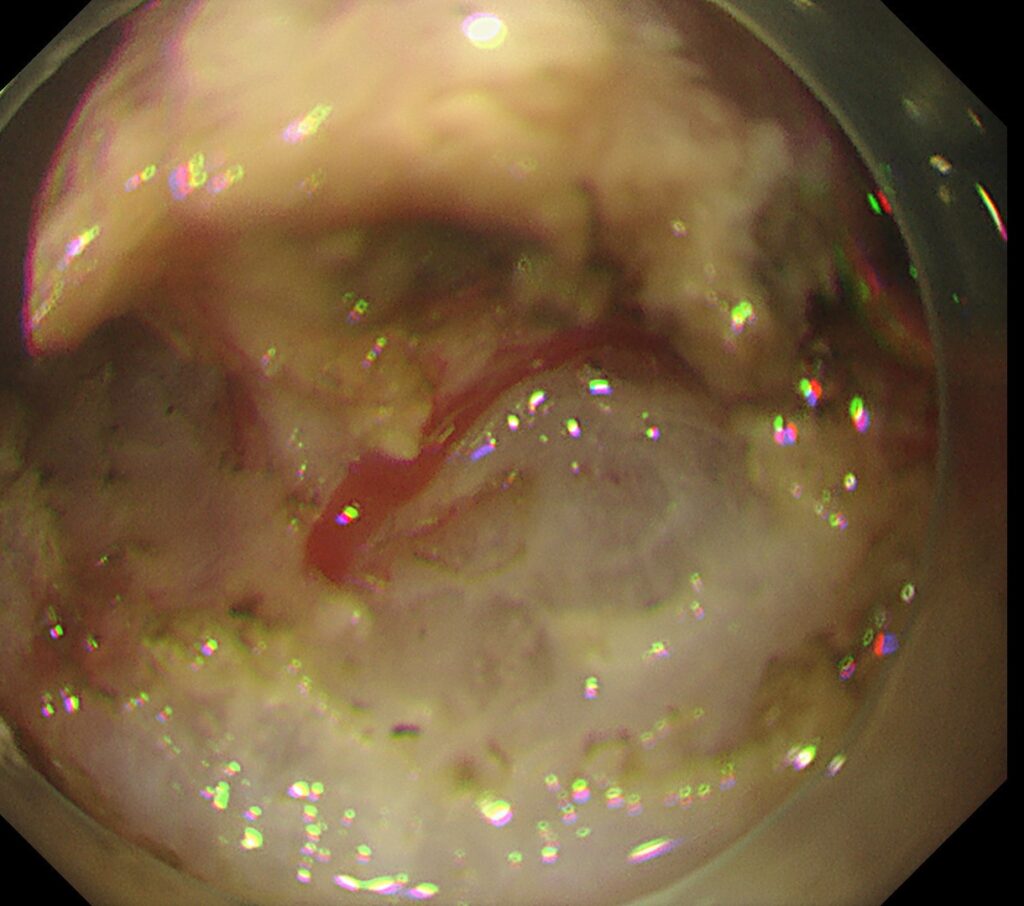

NBI観察では、高分化型腺癌(顔つきの良い癌)+中分化型腺癌(やや顔つきの悪い癌)の混在所見を認めます。